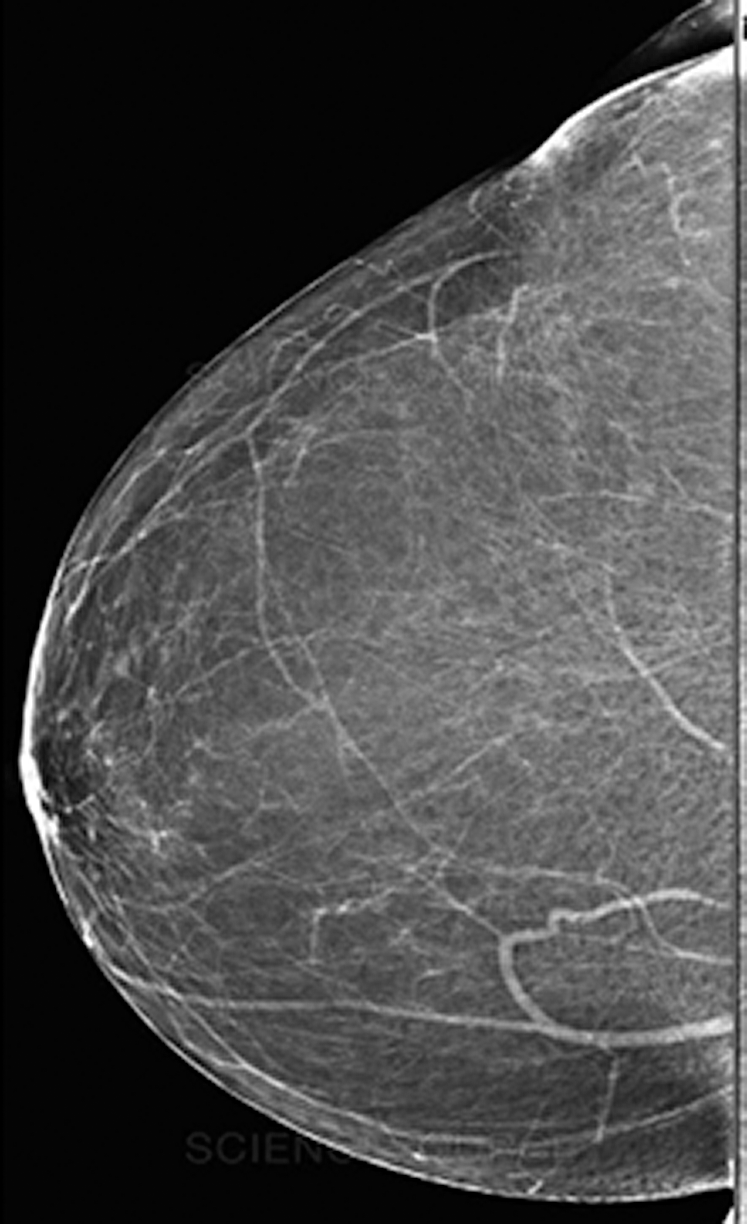

Fig. 7 depicts a mammogram image of a breast with normal tissues from the dataset DS, while Fig. 8 depicts a mammogram image from the DS dataset with cancer ROI that has been detected using T3. In Fig. 9, a mammogram is shown after applying texture features coupled with SIFT local features using T4.

Figure 7: A mammogram image of a breast with normal tissues

Figure 8: A mammogram image from the DS dataset with cancer ROI using T3